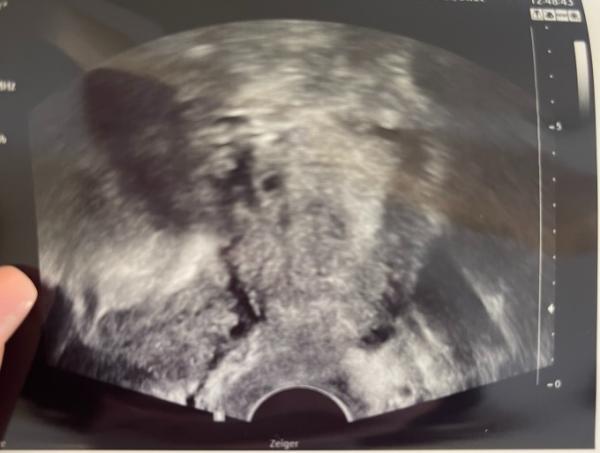

Dieses Bild ist vom Dienstag da soll ich 5+5 sein Das Bild oben vom Freitag

Bild zu

Jedes Praxis hat einen anderen Ultraschall gerät. Das sollte man auch beachten. Während die einen ein gestochen scharfes Bild bekommen, bekommen die anderen ein ratebild.

Mein Bild bei 5+6 sah anders aus, aber was bringt dir das jetzt? Der Arzt sagt, alles ist gut und alle Werte sind gut, dann ist doch alles gut. Vielleicht bist du auch einfach ein paar Tage früher als du denkst oder die Geräte bei deinem FA sind nicht so gut, es kann an so vielen Dingen liegen. Ich würde mich immer auf die Meinung des Arztes verlassen und nicht auf Google oder andere Ss.